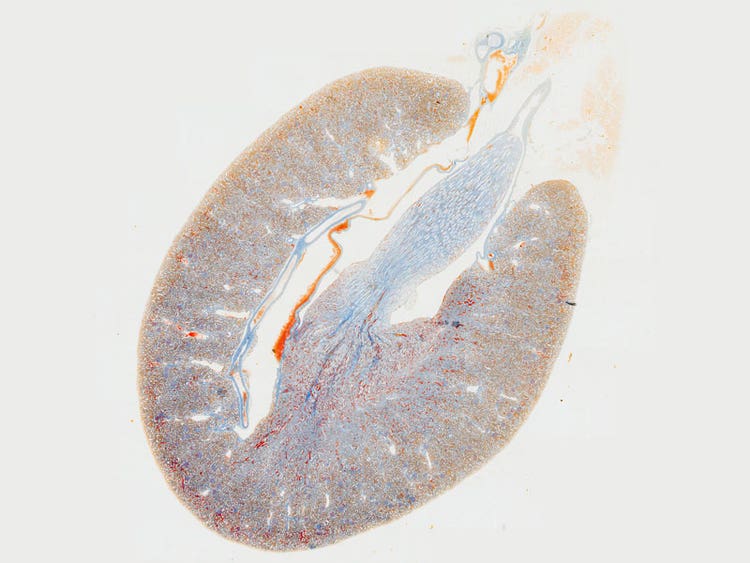

Observation FISH

Amélioration des images pour les applications de recherche clinique

Ensemble, l'amélioration de la planéité, l'ouverture numérique et l'aberration chromatique permettent de fournir des images claires de haute résolution avec une excellente reproduction des couleurs. La gestion de l'aberration chromatique assure des couleurs plus précises sur l'ensemble du spectre. L'élimination de l'aberration de la couleur violette crée des blancs clairs et des roses vifs, et améliore le contraste et la netteté. La correction de l'aberration chromatique sur une grande plage de longueurs d'onde (400-1 000 nm) vous permet d'acquérir des images multicolores de haute résolution pendant une observation par fluorescence, telle que FISH.